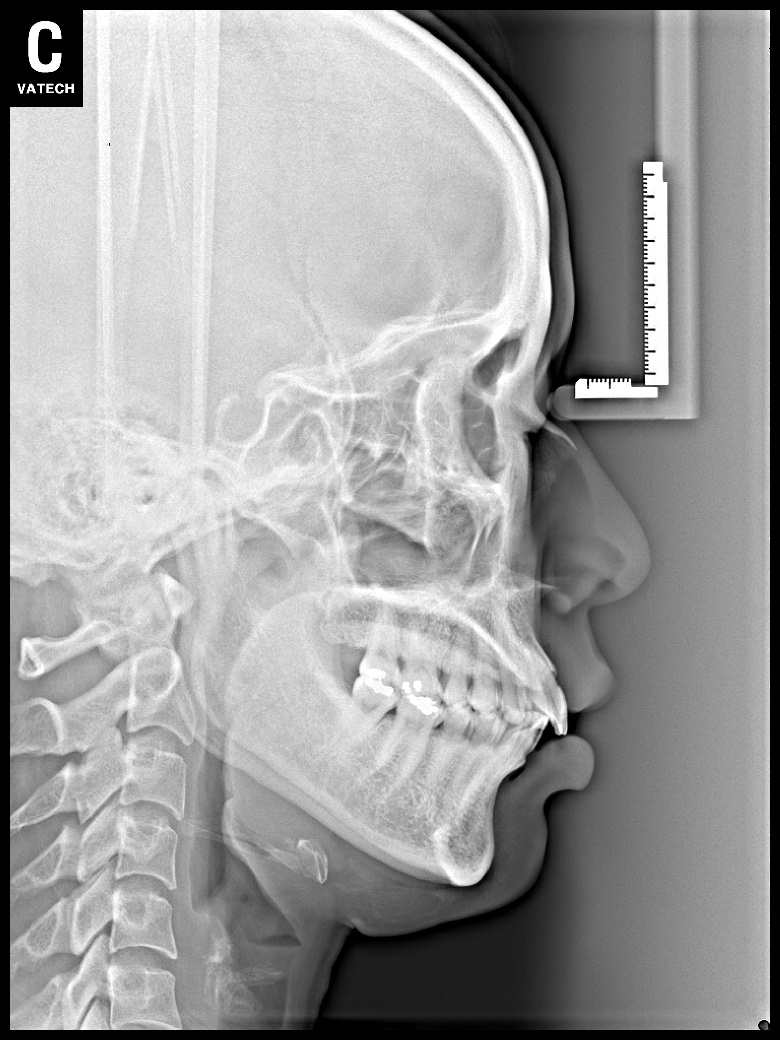

치료 후 사진입니다.